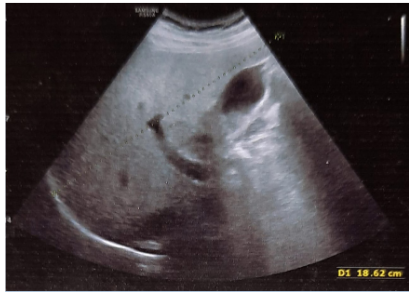

A 35-years-old non-smoker, non-alcoholic, non-vegetarian, menstruating female presented with moderate to severe spasmodic pain in right upper abdomen and epigastric region for one year. Pain was aggravated after the fatty and spicy meal. There was history of several episodes of vomiting during attack of severe pain in last three month which occurred typically in night after 2-3hours of heavy meal. Vomiting was bilious in nature. She took antacids, H2 blockers, proton pump inhibitors and antiemetic along with pain killers but could not be improved. She had a history of hospital admission for once six months before. The patient was referred to us for the laparoscopic cholecystectomy. The patient was then thoroughly examined and nothing significant could be detected in systemic but on local examination, hepatomegaly was found with palpable gallbladder. Ultrasonography (USG) abdomen Figure 4 showed large over-distended gallbladder with mild wall thickness and thick sludge and concretions in the lumen. The blood biochemistry revealed high total leukocyte counts (14800/cumm) with neutrophilia (82%). Serology showed raised Alkaline phosphatase (325 U/L), Aspartate transaminase (AST) 89 IU/L and Alanine aminotransferase (ALT) 142 IU/L. Rest of the lab parameters were within normal limits. Patient was given OmlivTM, one tablet twice daily along with broad-spectrum antibiotics and PPIs. Antibiotics and PPIs were stopped after 7days when TLC became normal (7300/cumm) and the OmlivTM, one tablet twice daily continued for the complete 45 days therapy. The follow-up USG (Figure 5) revealed normally distended gallbladder with normal wall thickness and clear lumen. There was no evidence of sludge or concretions in the gallbladder lumen. Blood biochemistry and abnormal liver function tests also come within normal limits.

Figure 4 Case No. 2 [Pre-treatment ultrasonography scan showing biliary sludge & concretions].

Figure 5 Case No. 2 [Post-treatment ultrasonography scan showing clear gallbladder lumen].